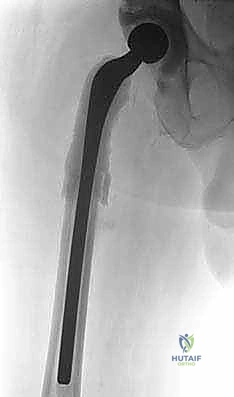

المرحلة الثانية: إعادة البناء وتركيب المفصل النهائي (Re-implantation)

بعد التأكد التام من القضاء على العدوى (سريرياً ومخبرياً)، وتوقف المريض عن تناول المضادات الحيوية لمدة أسبوعين على